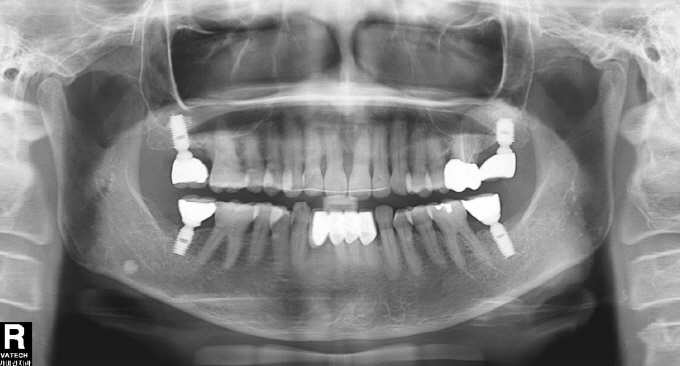

| Fig. 2: 62¼¼ ¿©ÀÚ, Àå±â°£ Ä¡ÁÖ±³Á¤Ä¡·á¸¦ ¸¶ÃÆ°í º¸Ã¶Ä¡·á¿Í ÀÓÇöõƮġ·á±îÁö ÀüºÎ ¿Ï¼ºÇÏ¿´´Ù. |